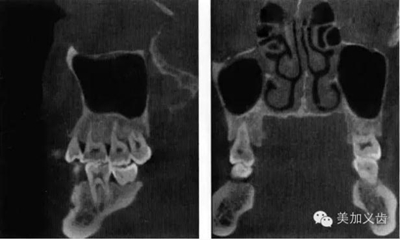

——錐形束CT

這個是三維放射線重建影像可以全面、準(zhǔn)確的評價解剖學(xué)結(jié)構(gòu),包括可用骨形態(tài)的三維數(shù)值,通俗點講就是可以看到可用骨的垂直向、近遠中向和頰舌向的數(shù)值。

其優(yōu)點是:可以提供精確的、亞毫米級測量數(shù)值,與印模結(jié)合,通過CBCT數(shù)據(jù)來實現(xiàn)模擬手術(shù)并制作外科導(dǎo)板。CBCT的放射量與傳統(tǒng)CT相比要小很多,放射時間短,操作也比較簡單。

現(xiàn)在很多廠家都能夠制作外科導(dǎo)板了,醫(yī)生把CBCT數(shù)據(jù)和石膏模型發(fā)送給加工廠,加工廠通過軟件設(shè)計來進行虛擬種植,就能通過3D打印技術(shù)或者CAD/CAM做出手術(shù)導(dǎo)板。你不用管他們是怎么做的,總之你能得到一個手術(shù)導(dǎo)板,有了導(dǎo)板的幫助,種植手術(shù)的難度會降低很多,尤其是多顆牙的種植手術(shù)。

9.jpg

其缺點是:設(shè)備成本還是比較高,分辨率略顯不足,而且會存在一定程度上的影像學(xué)偽影。